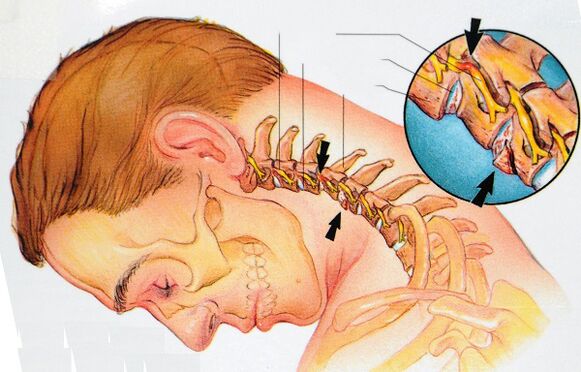

Kumpara sa iba pang mga kagawaran ng gulugod, ang rehiyon ng cervical ay ang pinaka -mobile at maraming mga nerbiyos at vascular formations. Ang istraktura ng vertebrae ay maliit sa laki, pati na rin ang katotohanan na sila ay napapaligiran ng isang medyo mahina na corset ng kalamnan.

Ang nasabing isang anatomical na istraktura ay nauna sa pag -unlad ng osteochondrosis, ang kalubhaan ng mga klinikal na pagpapakita na kung saan ay nakasalalay sa likas na katangian ng mga pagbabago sa mga intervertebral disc at ang antas ng pagkawasak.

Hindi lamang ang mga ugat ng spinal cord at nerve ay dumadaan sa cervical spine, kundi pati na rin ang vertebral artery, na responsable sa pagbibigay ng dugo ng likod ng utak, isang pahaba na utak at cerebellum.

Samakatuwid, na may cervical osteochondrosis, ang arterya na ito ay kinurot, at bilang isang resulta, isang paglabag sa sirkulasyon ng cerebral.

Sa partikular na mga advanced na kaso, ang pagpisil sa arterya at katabing mga daluyan ng dugo at mga plexus ng nerbiyos ay maaaring humantong sa mga kahihinatnan tulad ng: